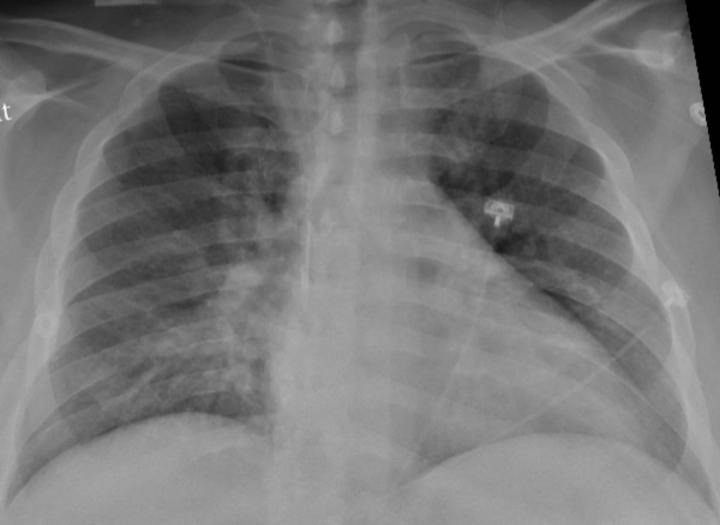

Un estudio explica por qué la neumonía por Covid-19 dura más y causa más daño

En lugar de infectar rápidamente grandes regiones del pulmón, el virus se instala en múltiples áreas pequeñas del pulmón. Luego secuestra las células inmunes de los pulmones y las utiliza para propagarse por el pulmón durante un período de muchos días o incluso semanas, como los múltiples incendios forestales que se propagan por un bosque. A medida que la infección se mueve lentamente a través del pulmón, deja daños a su paso y continuamente alimenta la fiebre, la baja presión sanguínea y los daños en los riñones, el cerebro, el corazón y otros órganos.